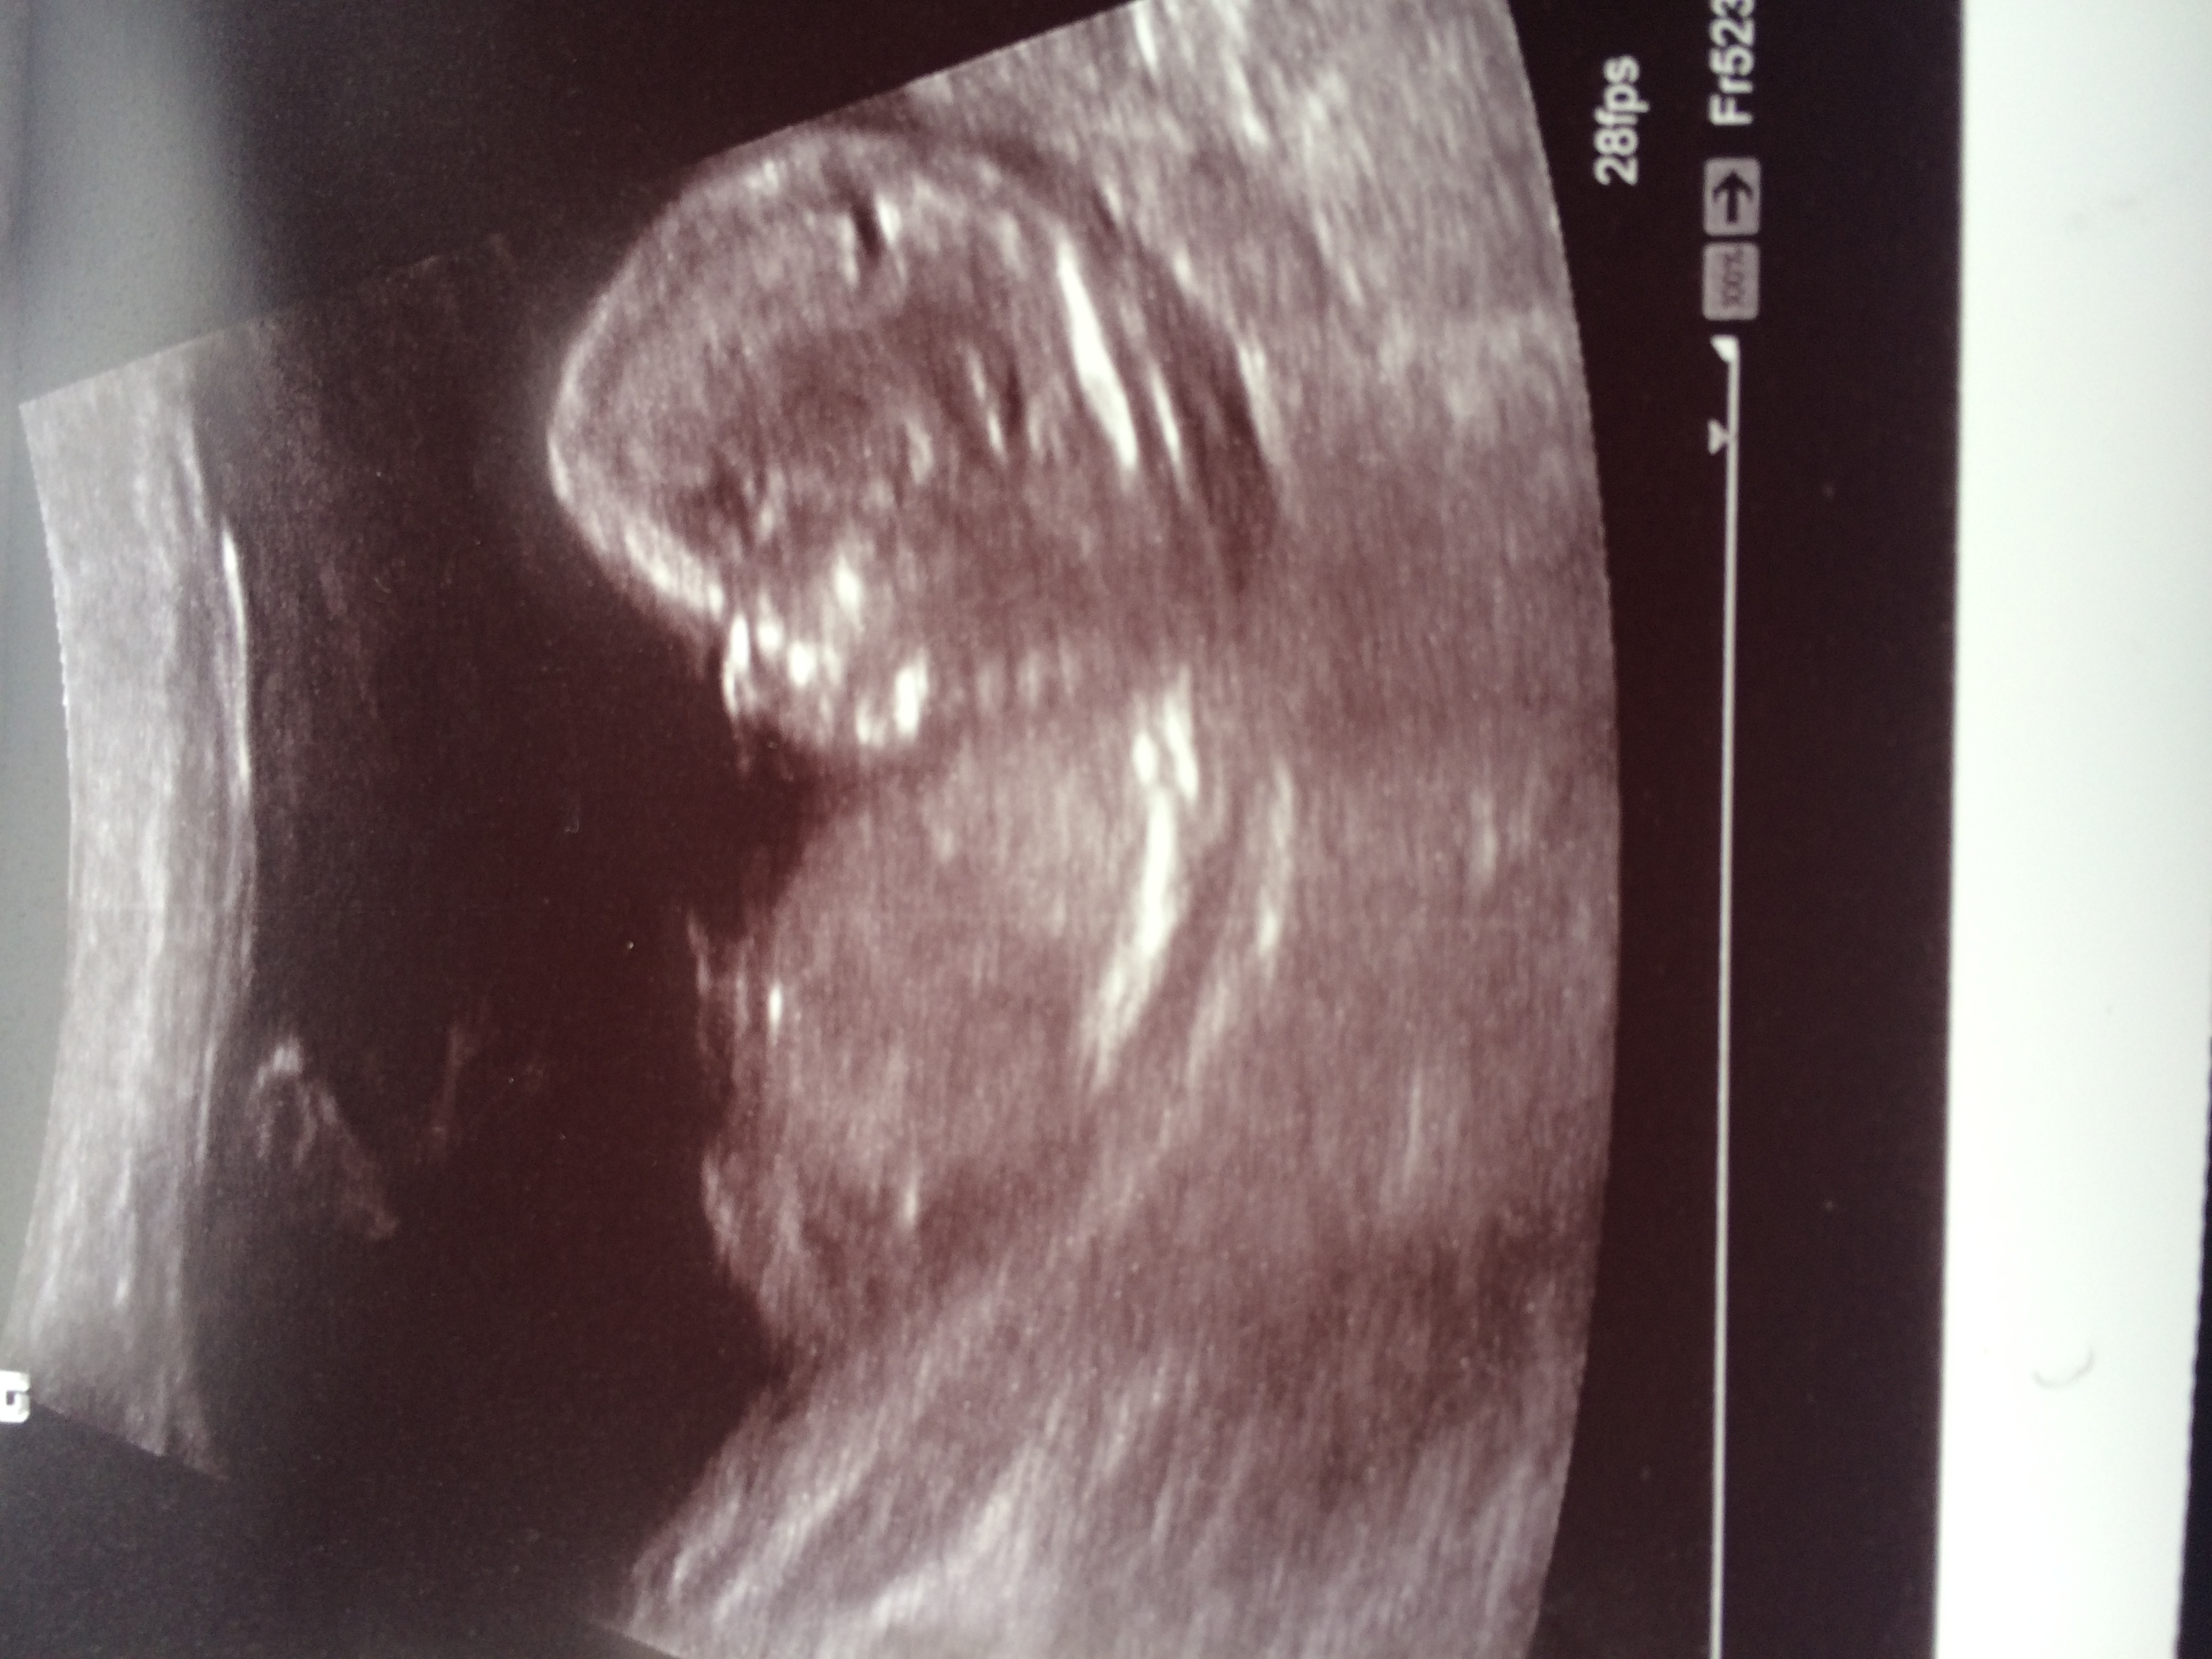

Hi this is my scan at 13w 1d. Does this look like a girl nub? Attachment 28089

I'm not sure if that's the nub. I think it's missed off this image. Have you got any others?

Looks like a girly nub to me as the spine is curved up and nub is protruding quite a lot

Boy and girl nubs can appear forked.